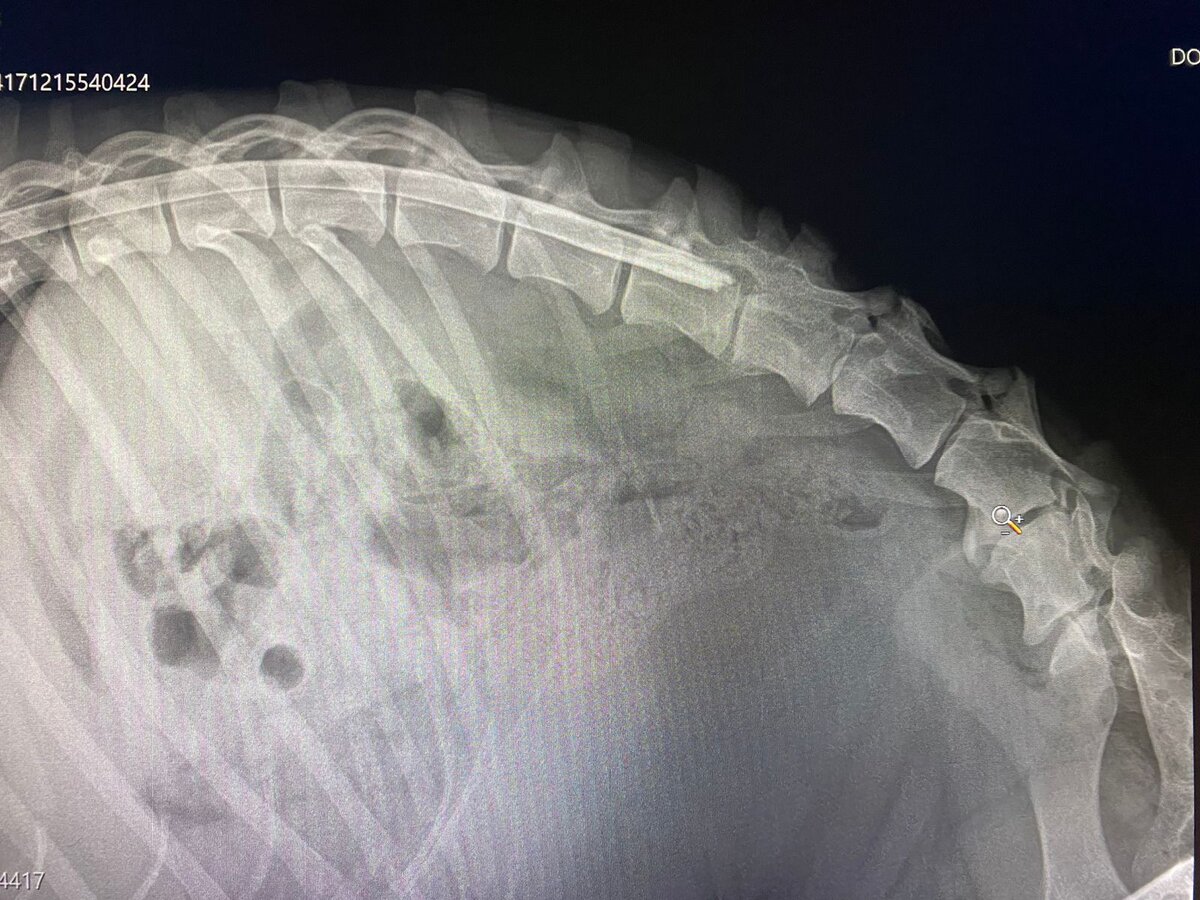

Свозили Черного в клинику. Нужна операция.

Сделали рентген и рентген позвоночника с контрастом.

У Черного застарелый перелом позвоночника и костей таза. Кости таза срослись неправильно.

В результате проведенных обследований Курбатов Д.В. сделал вывод, что у Черного есть шанс улучшить качество жизни. Чувствительность в одной лапе сохранена. Несмотря на то, что переломы застарелые, нам предложили сделать Черному операцию, которая сможет помочь поставить его на лапы.

Операция состоится в субботу в 11 часов. На операцию нам необходимо 15 000 рублей.